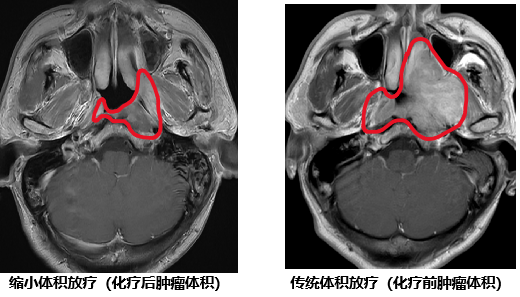

对于鼻咽癌的治疗,放射治疗是主要治疗手段。国际指南推荐,局部晚期鼻咽癌以“化疗+同期放化疗”的综合治疗。化疗使90%患者肿瘤显著缩小,而既往国际专家共识推荐放疗照射范围仍需包括化疗前肿瘤大小。这导致放疗时周围正常组织(如内耳、腮腺)接受高剂量辐射,引发口干、听力损伤等不可逆副作用,放疗相关毒性发生率高,严重影响患者生活质量。

研究团队采用多中心、随机、非劣效、平行对照设计,纳入445例III-IVa期局晚期鼻咽癌患者,先进行放疗前吉西他滨联合顺铂化疗3程,然后随机分为两组:

试验组:化疗后治疗范围放疗

对照组:化疗前肿瘤范围放疗